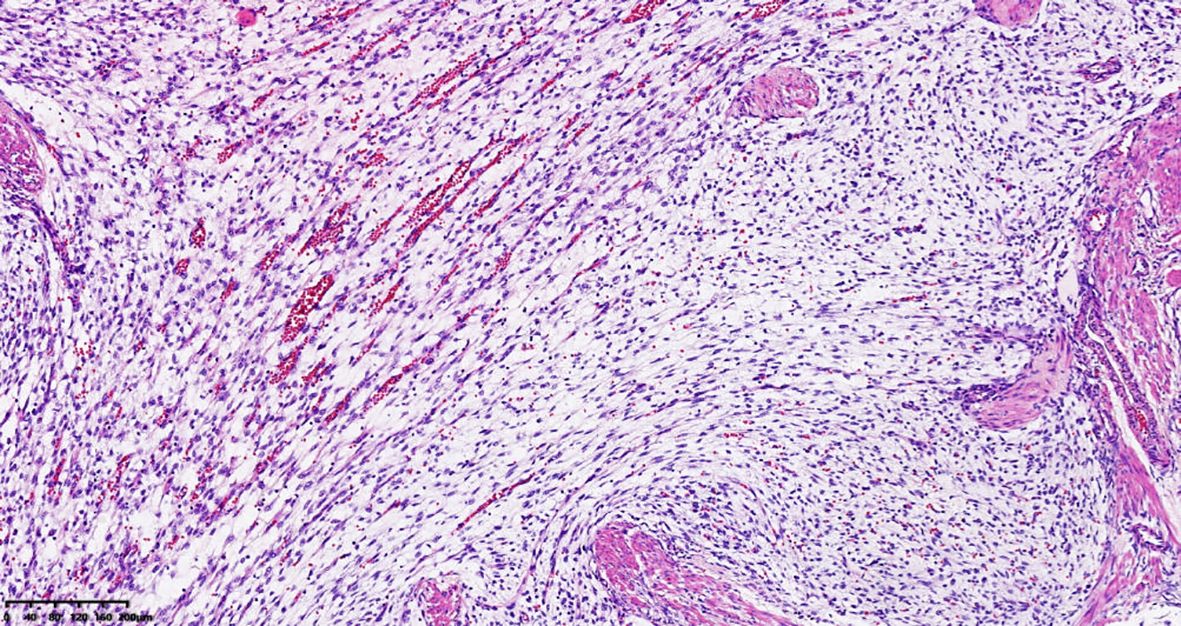

Plexiform fibromyxoma (PF) is a rare mesenchymal tumour that primarily occurs in the stomach, with the antrum and pyloric region being the most common sites. A few cases have also been reported in the duodenum, jejunum, mediastinum, gallbladder, and other locations. Over 100 cases have been reported in the literature, with more than 30 cases reported in our country. A rare case of PF occurring in the cardia and fundus of the stomach is reported in this study. The tumour tissue showed a multinodular, plexiform growth pattern between the muscle bundles of the gastric wall, in which a myxoid matrix and thin-walled vessels were visible. The tumour cells were spindle shaped or short spindle shaped, with a mild change in morphological appearance, and mitotic figures were rare. The tumour cells showed immunohistochemical expression of vimentin and SMA, with focal expression of calponin and CD10. The Ki-67 proliferation index was approximately 5%. The plexiform fibromyxoma was characterized by benign biological behaviour, with surgical excision as the primary therapy. The patient was followed up for about 2 years after surgery without any tumour recurrence or metastasis.